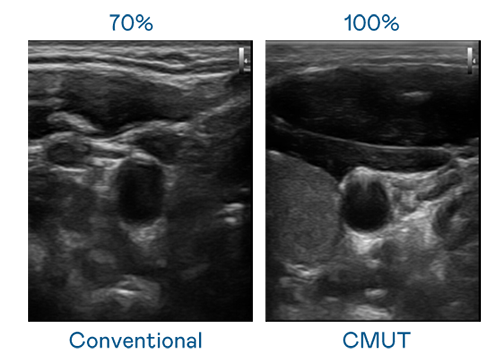

CMUT 技术是一种用电容式微机电元件来产生超音波讯号的技术。与传统 PZT 压电式技术相比,CMUT 频宽增加 30%,更宽频的超音波讯号让影像解析度大幅提升,是实现高影像品质医疗超音波扫描、促进精准医疗发展的关键技术。

大频宽带来超清晰影像

超音波影像的解析度高低,首先取决于探头能发出的讯号频宽。YABO鸭脖 CMUT 可提供高清晰的超音波讯号,提供高频宽、高灵敏度、影像纹理细节更高的超音波影像,协助医护人员缩短影像判读时间及利用精准的医疗影像进行诊断。